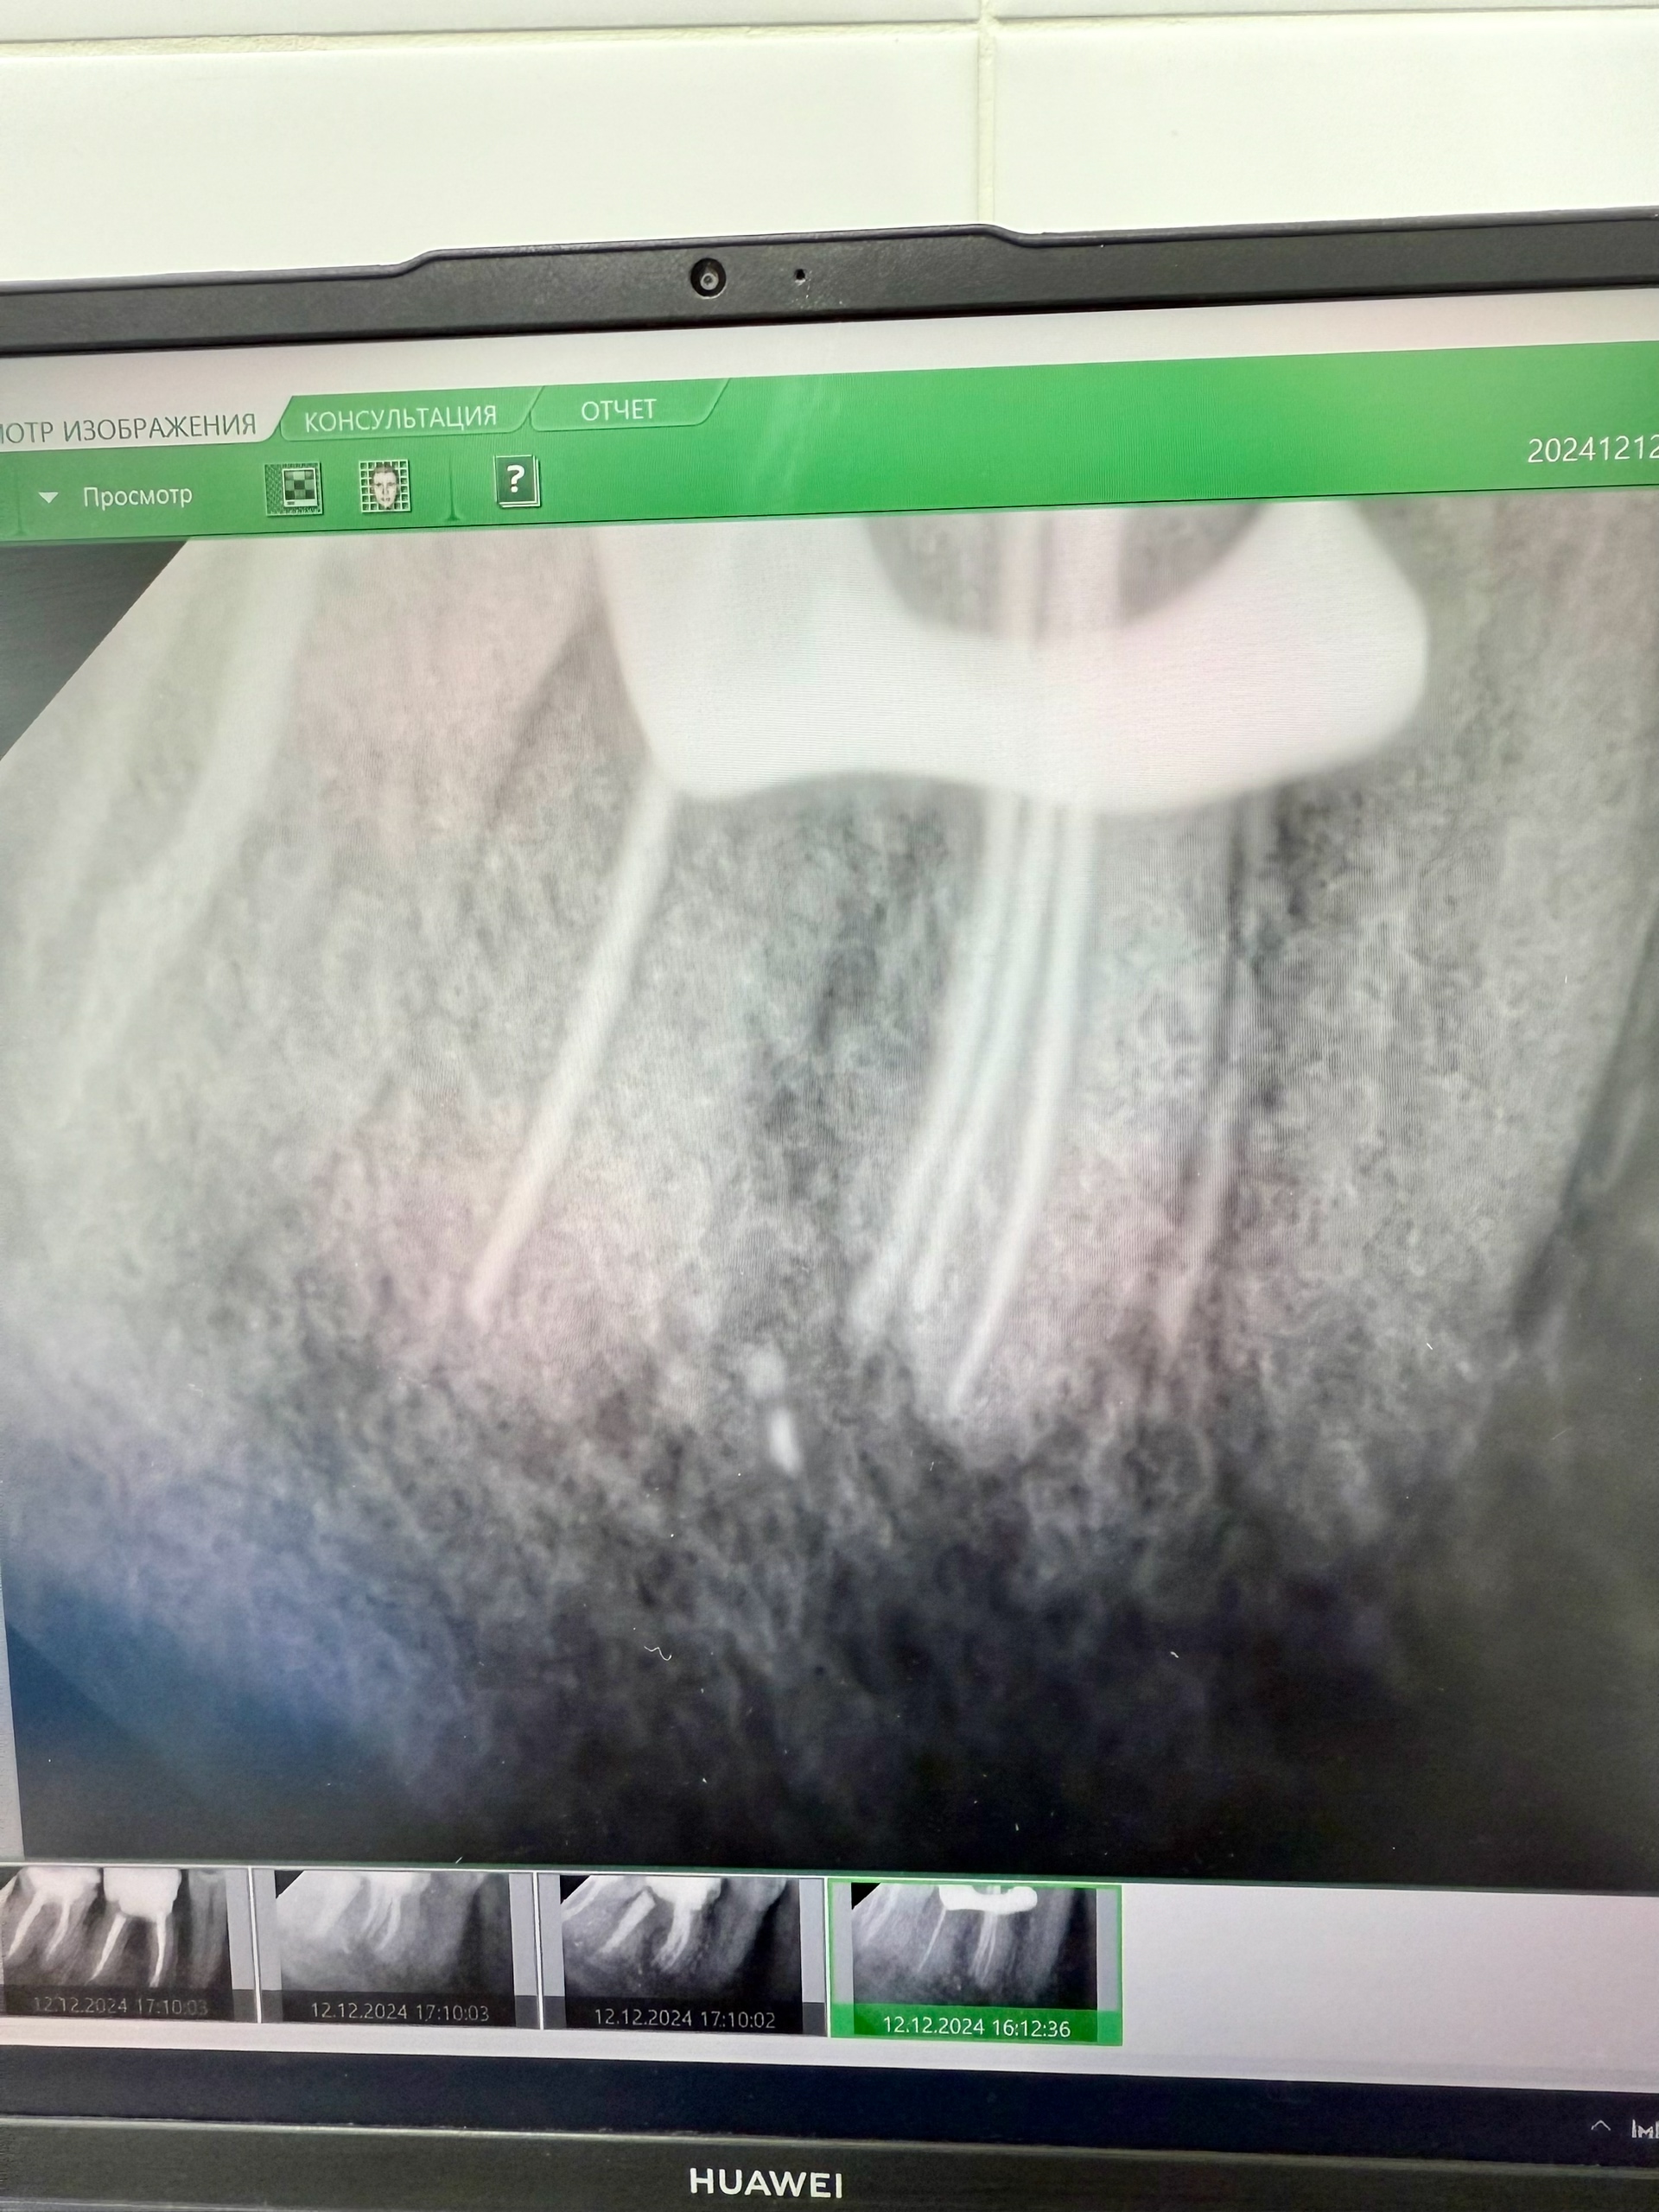

Всем привет! Сегодня, наконец, завершил этот случай, особенностью является то, что в зубе №36 (апикальный периодонтит).

1. Были пропущены два канала: мезиально щёчный и мезиально срединный. А также то, что все они отдельные каналы.

2. Пациентка пришла в обострение, здесь была и экспресс-диагностика на трещину (времени было мало, а пломба огромная) и разрез хирурга.

3. Но мы его успокоили, перелечили и отправили на временной коронки! Автор: Евгений Никулин